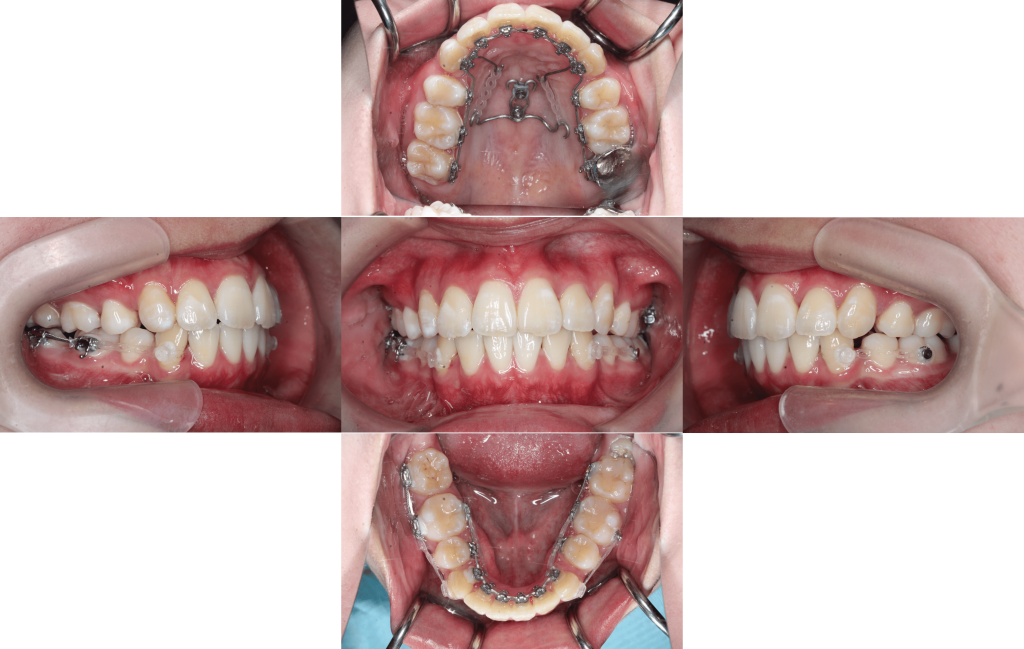

Before

After

初診

装置装着

約6か月後

約1年後

約1年6か月後

約2年後

約2年6か月後

約3年後

年齢層

20代

性別

女性

主訴

・1┴1でっぱり・凸凹な歯並び・Eライン・上下のかみ合わせ

治療費用

¥1,320,000

治療期間

約3年(治療中)

抜歯

上下顎両側第一小臼歯

矯正の装置

マルチブラケット装置(裏側矯正)

副作用、リスク

歯肉退縮,歯根吸収,疼痛,咬合の違和感,装置の違和感,虫歯,歯肉炎